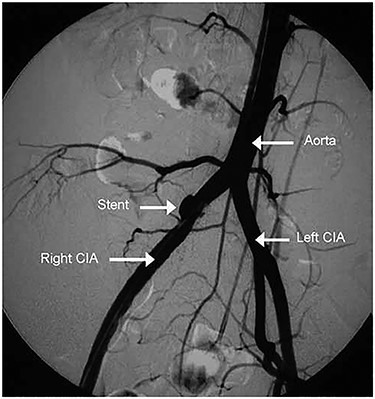

The patient underwent an endovascular repair of his AVF under spinal anesthesia. An Endurant (Medtronic, Inc., Minneapolis, MN) iliac stent graft was successfully deployed (Fig. 2). The patient had an IVC with a large diameter and low venous inflow owing to right lower limb DVT. Therefore, we decided to create an AVF at the groin with a limited inflow (200–300 mL/minute) between the common femoral vein and femoral artery using a tapered expanded polytetrafluoroethylene graft. The graft was closed after 3 months.

Post stent graft deployment angiogram showing the stent in position and the disappearance of AVF.

We performed endovascular repair using an Endurant stent graft. A stent was deployed without immediate complications, and the AVF was successfully sealed off. Surgical and endovascular repair of a large AVF can lead to dramatic hemodynamic changes. An immediate rise in systemic vascular resistance, decrease in central venous pressure, and decrease in central mixed venous oxygenation can occur. Our patient had an IVC with a 7 cm diameter and a right lower limb DVT. We were concerned about the stent graft patency owing to weak inflow. Therefore, we decided to create a limited inflow fistula between the femoral vein and femoral artery to promote venous patency. We closed it after 3 months. The patient’s symptoms dramatically improved after 6 months.